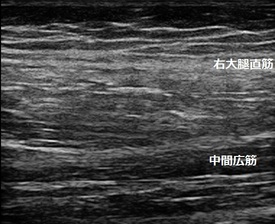

川越市 小学生 もも(大腿)の痛み 筋膜損傷

右もも(大腿部)患部 左もも(同部)正常側 右もも患部3週間後

膝の屈伸をしてもらうと痛みでゆっくりでしかできません。超音波検査で右もも前面の筋肉の

筋周膜(筋肉の縞模様)が正常側に比べて擦り切れ(損傷し)ていました(左画像の丸の囲み)。

小学生は普段サッカー少年団に所属しています。サッカーの練習に加えて、マラソン大会に向けて

ランニングをしていたため筋肉が疲労し、硬くなって筋周膜が擦り切れてしまいました。

筋肉の修復を促し柔軟にする理学療法を行います。日常生活では通学や階段昇降で痛みを

感じなくなるまで運動を休止します。

3週間後、右もも筋肉の筋周膜が修復されてきて、縞模様が視覚的に確認できるようになりました(右画像)。